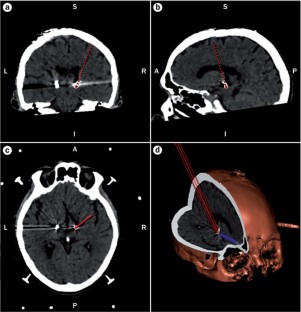

DBS of the posterior hypothalamus, subthalamic nucleus (STN) and periaqueductal grey (PAG) can cause changes in cardiovascular indices at rest and during postural challenge

Green, A. L. et al. Deep brain stimulation can regulate arterial blood pressure in awake humans. Neuroreport 16, 1741–1745 (2005).

Thornton, J. M., Aziz, T. Z., Schlugman, D. & Paterson, D. J. Electrical stimulation of the midbrain increases heart rate and arterial blood pressure in awake humans. J. Physiol. 539, 615–621 (2002).

Green, A. L. et al. Intra-operative deep brain stimulation of the periaqueductal grey matter modulates blood pressure and heart rate variability in humans. Neuromodulation 3, 174–181 (2010).

Green, A. L. et al. Controlling the heart via the brain: a potential new therapy for orthostatic hypotension. Neurosurgery 58, 1176–1183 (2006).

Patel, N. K. et al. Deep brain stimulation relieves refractory hypertension. Neurology 76, 405–407 (2010).

Green, A. L. et al. Stimulating the human midbrain to reveal the link between pain and blood pressure. Pain 3, 349–359 (2006).